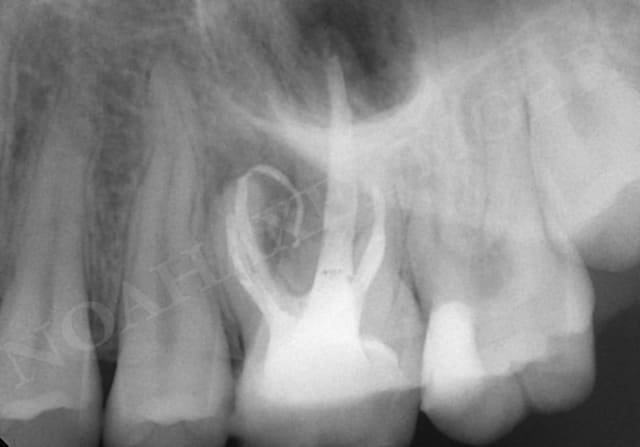

cas clinique avec abord transantral:

Comme il a été mentionné plus haut, la racine palatine des molaires maxillaires pose un problème spécial pendant les procédures de chirurgie endodontique.

Ces racines sont 50% plus près du sinus qu'elles sont du palais (Wallace 1996), montrent une communication apicale avec le sinus dans 20% du temps et sont à moins de 0.5 millimètre du sinus dans 40% du temps (Watzek 1997).

Pour ces raisons l'approche transantrale peut être vue comme une option souhaitable. Cette technique a été décrite et avec succès employée par plusieurs auteurs (Altonen 1975, Wallace 1996 - désolé pour la biblio ancienne mais ce sont des articles de références).

L’élevation de la membrane sinusienne est pratiquée en profondeur jusqu’à atteindre la proéminence de la racine palatine. La suite de l’intervention est pratiquée sous microscope opératoire : la mince couche osseuse recouvrant l’apex palatin est retirée avec un ciseau à os. La racine est réséquée au niveau désiré, l'extrémité de la racine est préparée avec un rétrotip ultrasonique selon les principes de la chirurgie endodontique apicale. L’obturation à rétro se fait avec du MTA.